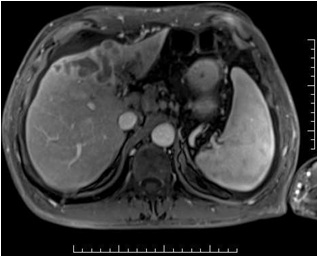

女 75 肝癌

肝左叶染色和栓塞